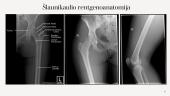

1. iliac crest 2. posterior superior iliac

spine 3. ilium 4. anterior sacral foramina 5. sacroiliac joint 6. sacral arcuate lines 7. anterior superior iliac

spine 8. anterior inferior iliac spine 9. ischial spine 10.superior pubic ramus 11.obturator foramen 12.ischium 13.ischial tuberosity

Klubo sąnario rentgenoanatomija

Frontal Lateral

14. symphysis pubis 15. coccyx 16. femur 17. lesser trochanter 18. greater trochanter 19. femoral neck 20. femoral head 21. acetabulum 22. fovea centralis 23. Koehler's teardrop 24.psoas fat pad 25. Intertrochanteric crest 26. gluteal fat pad 4